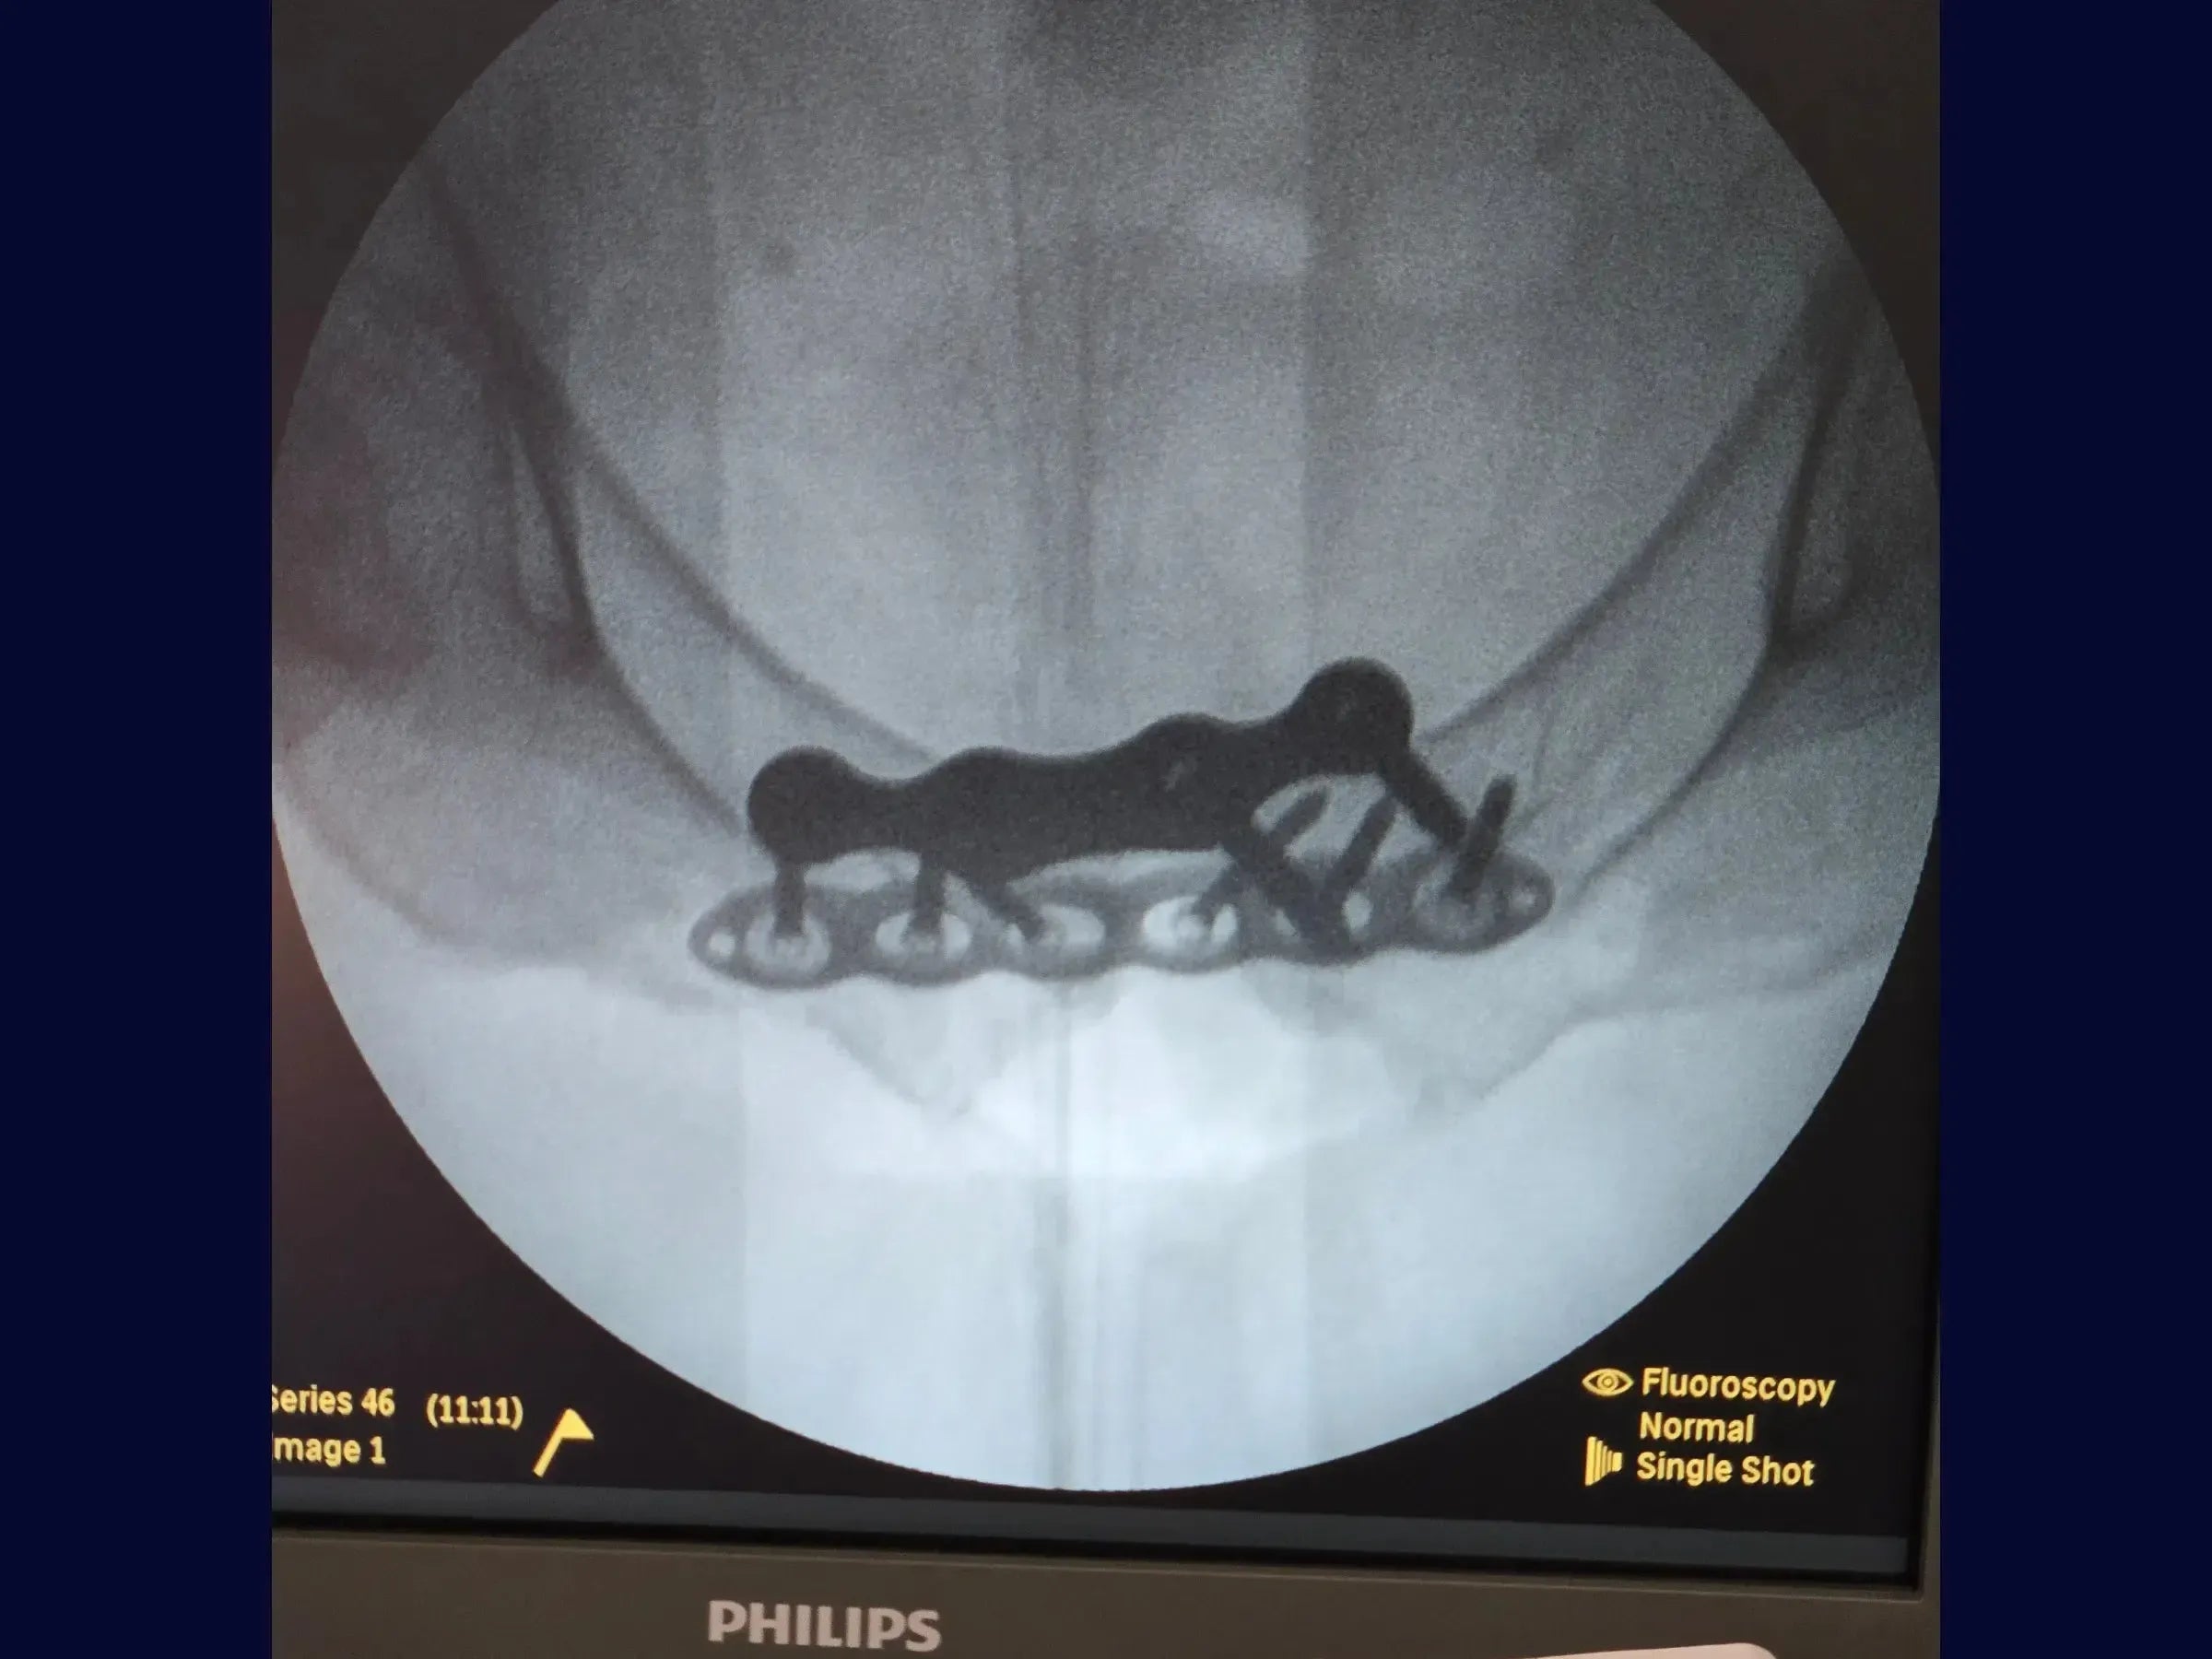

- Redução Provisória: Utilize parafusos temporários, um de cada lado da sínfise, inseridos de anterior para posterior com medição precisa. Empregue uma pinça específica acoplada a esses parafusos para redução e ajuste, controlando o cisalhamento e abertura visualmente.

- Fixação Definitiva: Com a redução mantida, use uma placa específica para a sínfise com introdução dos parafusos em angulação de 30 graus. Se parafusos não bloqueados não estiverem firmes, adicione uma segunda placa bloqueada anteriormente para maior estabilidade.